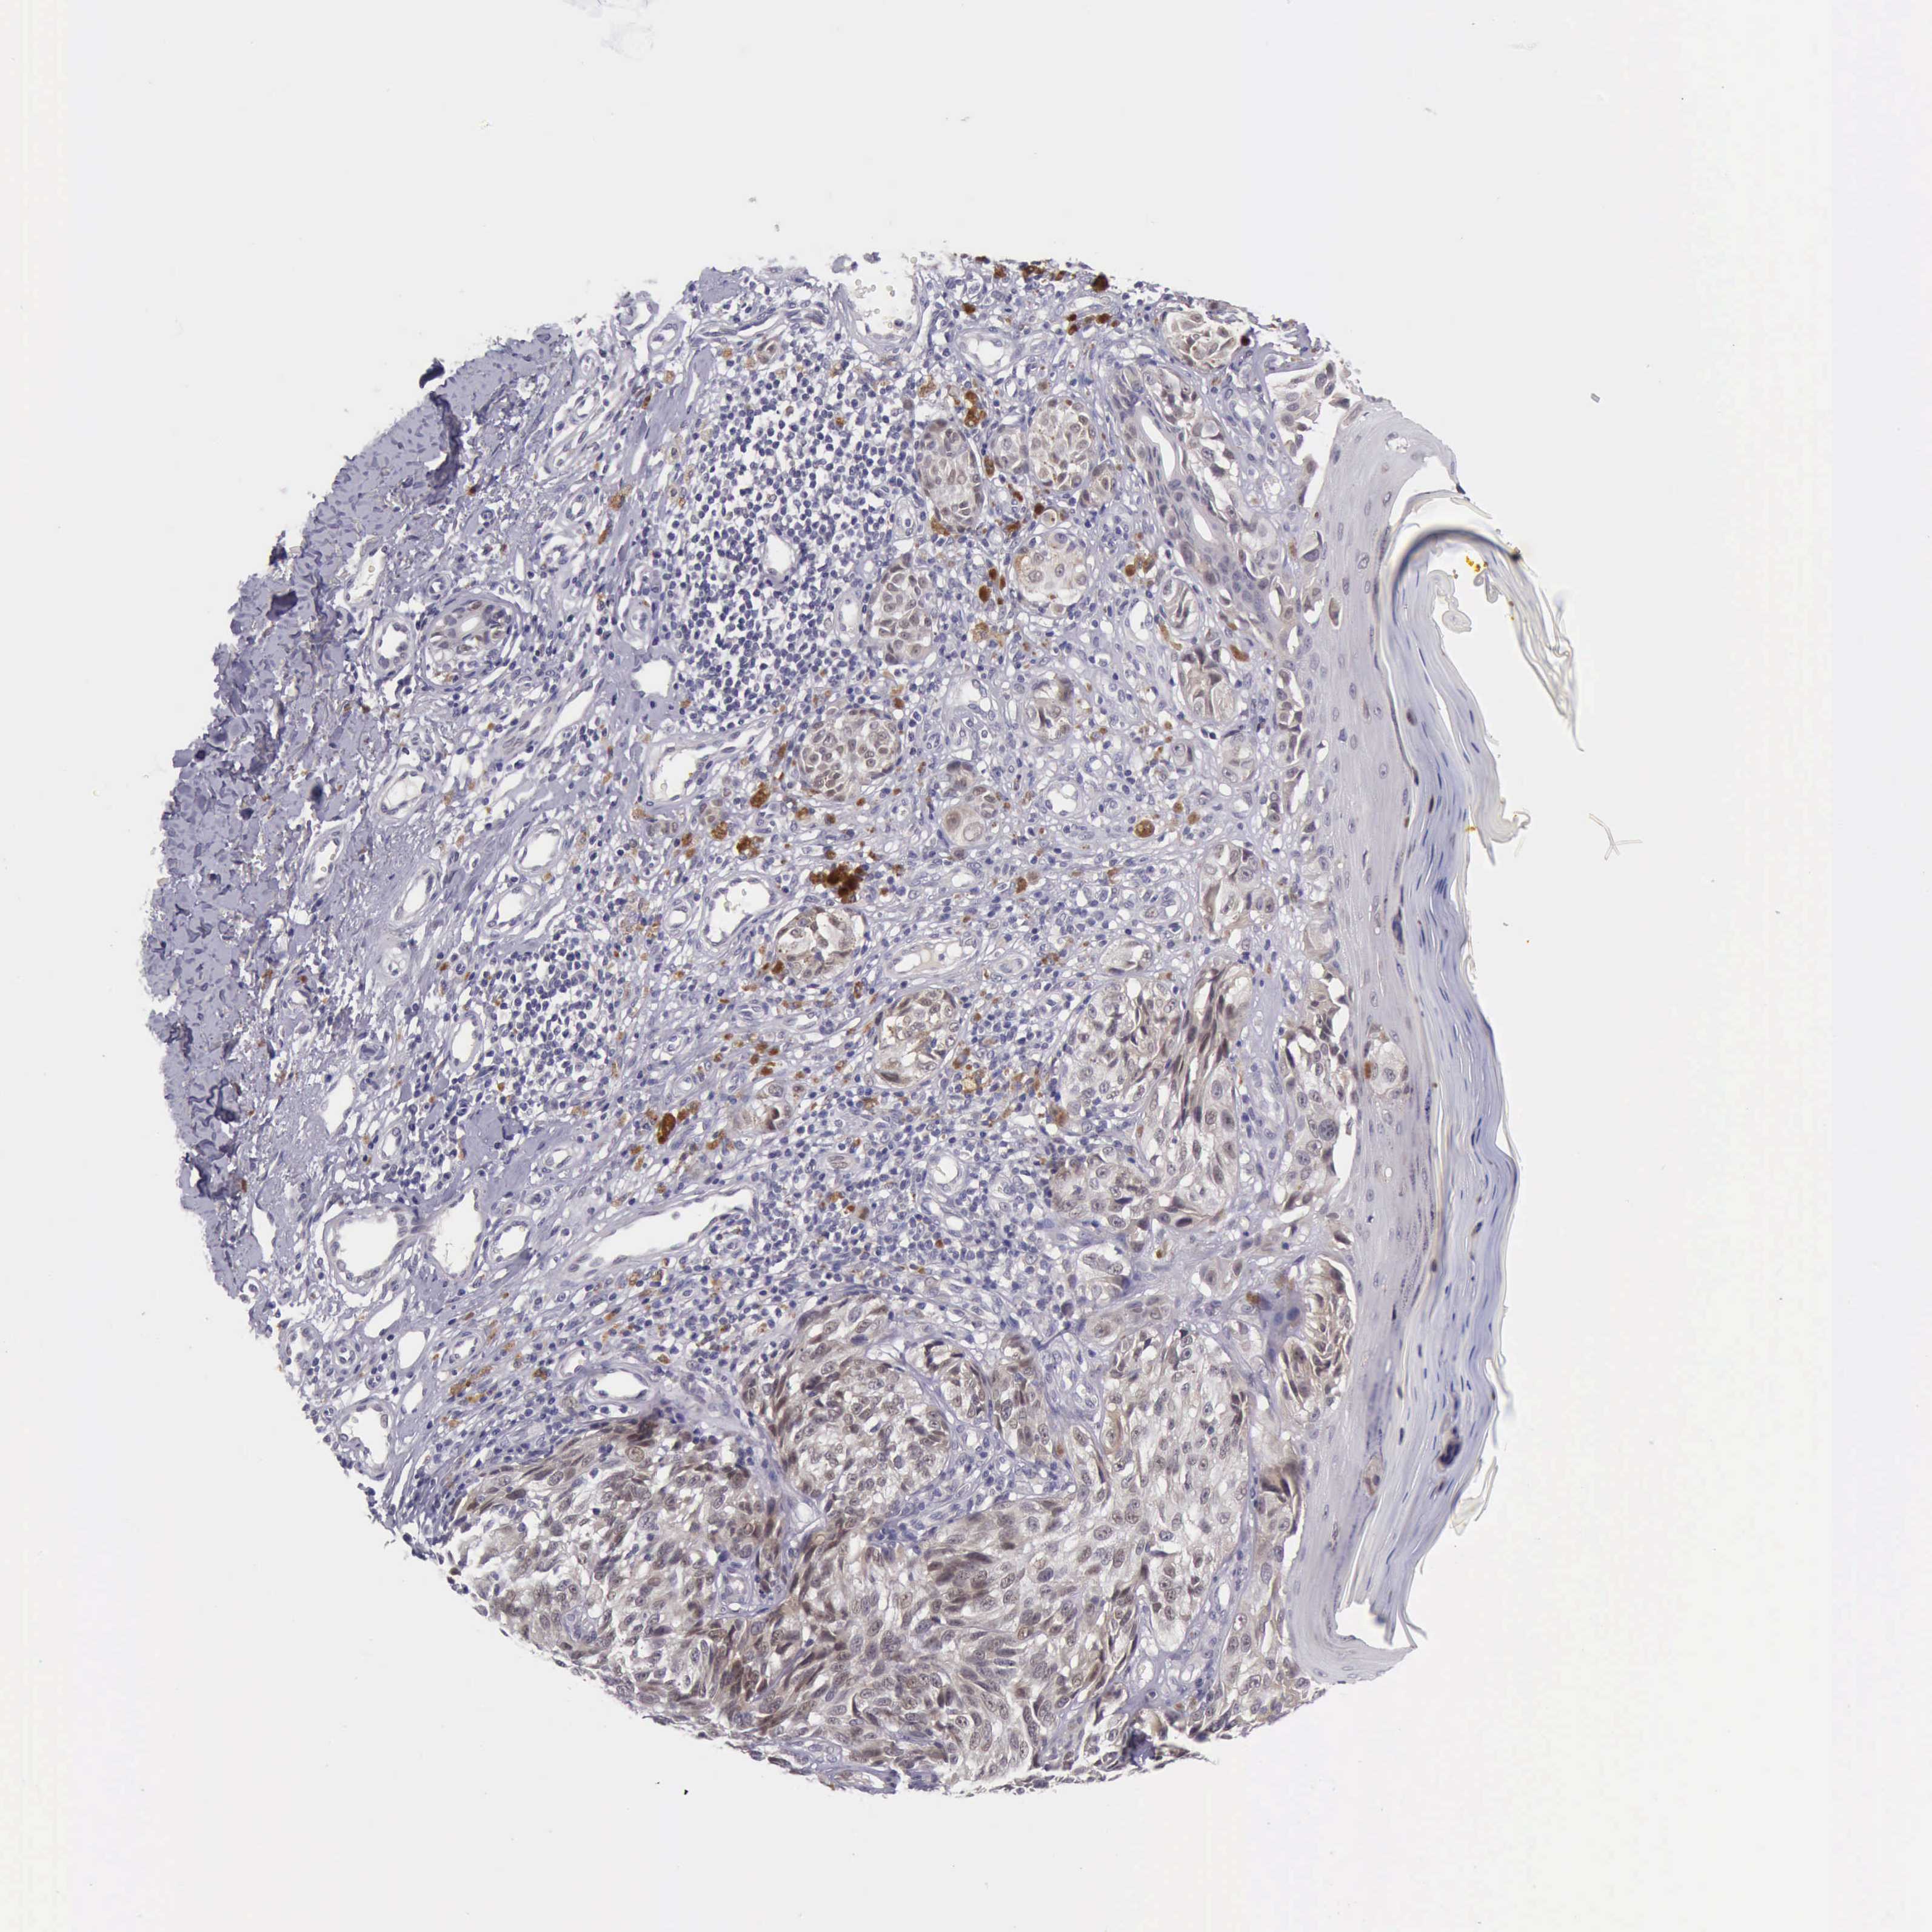

MELANOMA - Protein expressioni

A mouse-over function shows sample information and annotation data. Click on an image to view it in a full screen mode. Samples can be filtered based on level of antibody staining by selecting one or several of the following categories: high, medium, low and not detected. The assay and annotation is described here.

Note that samples used for immunohistochemistry by the Human Protein Atlas do not correspond to samples in the TCGA dataset.

Antibody stainingi

Antibody staining in the annotated cell types in the current human tissue is reported as not detected, low, medium, or high, based on conventional immunohistochemistry profiling in selected tissues. This score is based on the combination of the staining intensity and fraction of stained cells.

Each image is clickable and will lead to virtual microscopy that enables deeper exploration of all samples and also displays staining intensity scores, fraction scores and subcellular localization as well as patient and tissue information for each sample.

Antibody HPA001056

Antibody CAB005081

Staining

High

Medium

Low

Not detected

Intensity

Strong

Moderate

Weak

Negative

Quantity

>75%

75%-25%

<25%

None

Location

Nuclear

Cytoplasmic/membranous

Cytoplasmic/membranous,nuclear

Malignant melanoma, NOS

Malignant melanoma, Metastatic site